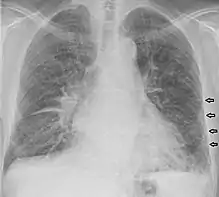

Kerley B lines in a patient with congestive heart failure.

- Kerley B lines

- These are short parallel lines at the lung periphery. These lines represent interlobular septa, which are usually less than 1 cm in length and parallel to one another at right angles to the pleura. They are located peripherally in contact with the pleura, but are generally absent along fissural surfaces. They may be seen in any zone but are most frequently observed at the lung bases at the costophrenic angles on the PA radiograph, and in the substernal region on lateral radiographs.[3] Causes of Kerley B lines include pulmonary edema, lymphangitis carcinomatosa and malignant lymphoma, viral and mycoplasmal pneumonia, interstitial pulmonary fibrosis, pneumoconiosis, and sarcoidosis. They can be an evanescent sign on the chest x-ray of a patient in and out of heart failure.